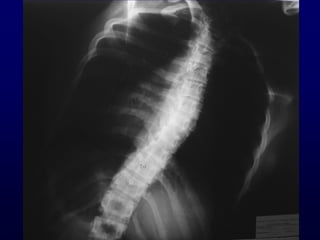

X-Rays

• Αηηημιμγία θαη ηύπμξ ηεξ παναμόνθςζεξ.

• Γκηόπηζε, έθηαζε θαη εοθαμρία ημο θονηώμαημξ.

• ΢οκμδέξ ζογγεκείξ παναμμνθώζεηξ

• ΢θειεηηθή ςνίμακζε.

Σμ πηό πμιύηημμ δηαγκςζηηθό ενγαιείμ.

AP

Απόζηαζε 2 m

Films: 36 x 91 cm

36 x 43 cm

Σ1 - S1

Ημνμόξ: Χςνίξ ζηνμθή

Δηόνζςζε ακηζμζθειίαξ

X-Rays • Αηηημιμγία θαηηύπμξ ηεξ παναμόνθςζεξ. • Γκηόπηζε, έθηαζε θαη εοθαμρία ημο θονηώμαημξ. • ΢οκμδέξ ζογγεκείξ παναμμνθώζεηξ • ΢θειεηηθή ςνίμακζε. Σμ πηό πμιύηημμ δηαγκςζηηθό ενγαιείμ.

AP Απόζηαζε 2 m Films:36 x 91 cm 36 x 43 cm Σ1 - S1 Ημνμόξ: Χςνίξ ζηνμθή Δηόνζςζε ακηζμζθειίαξ X-Rays LATERAL Ηάμρε ώμςκ 90°